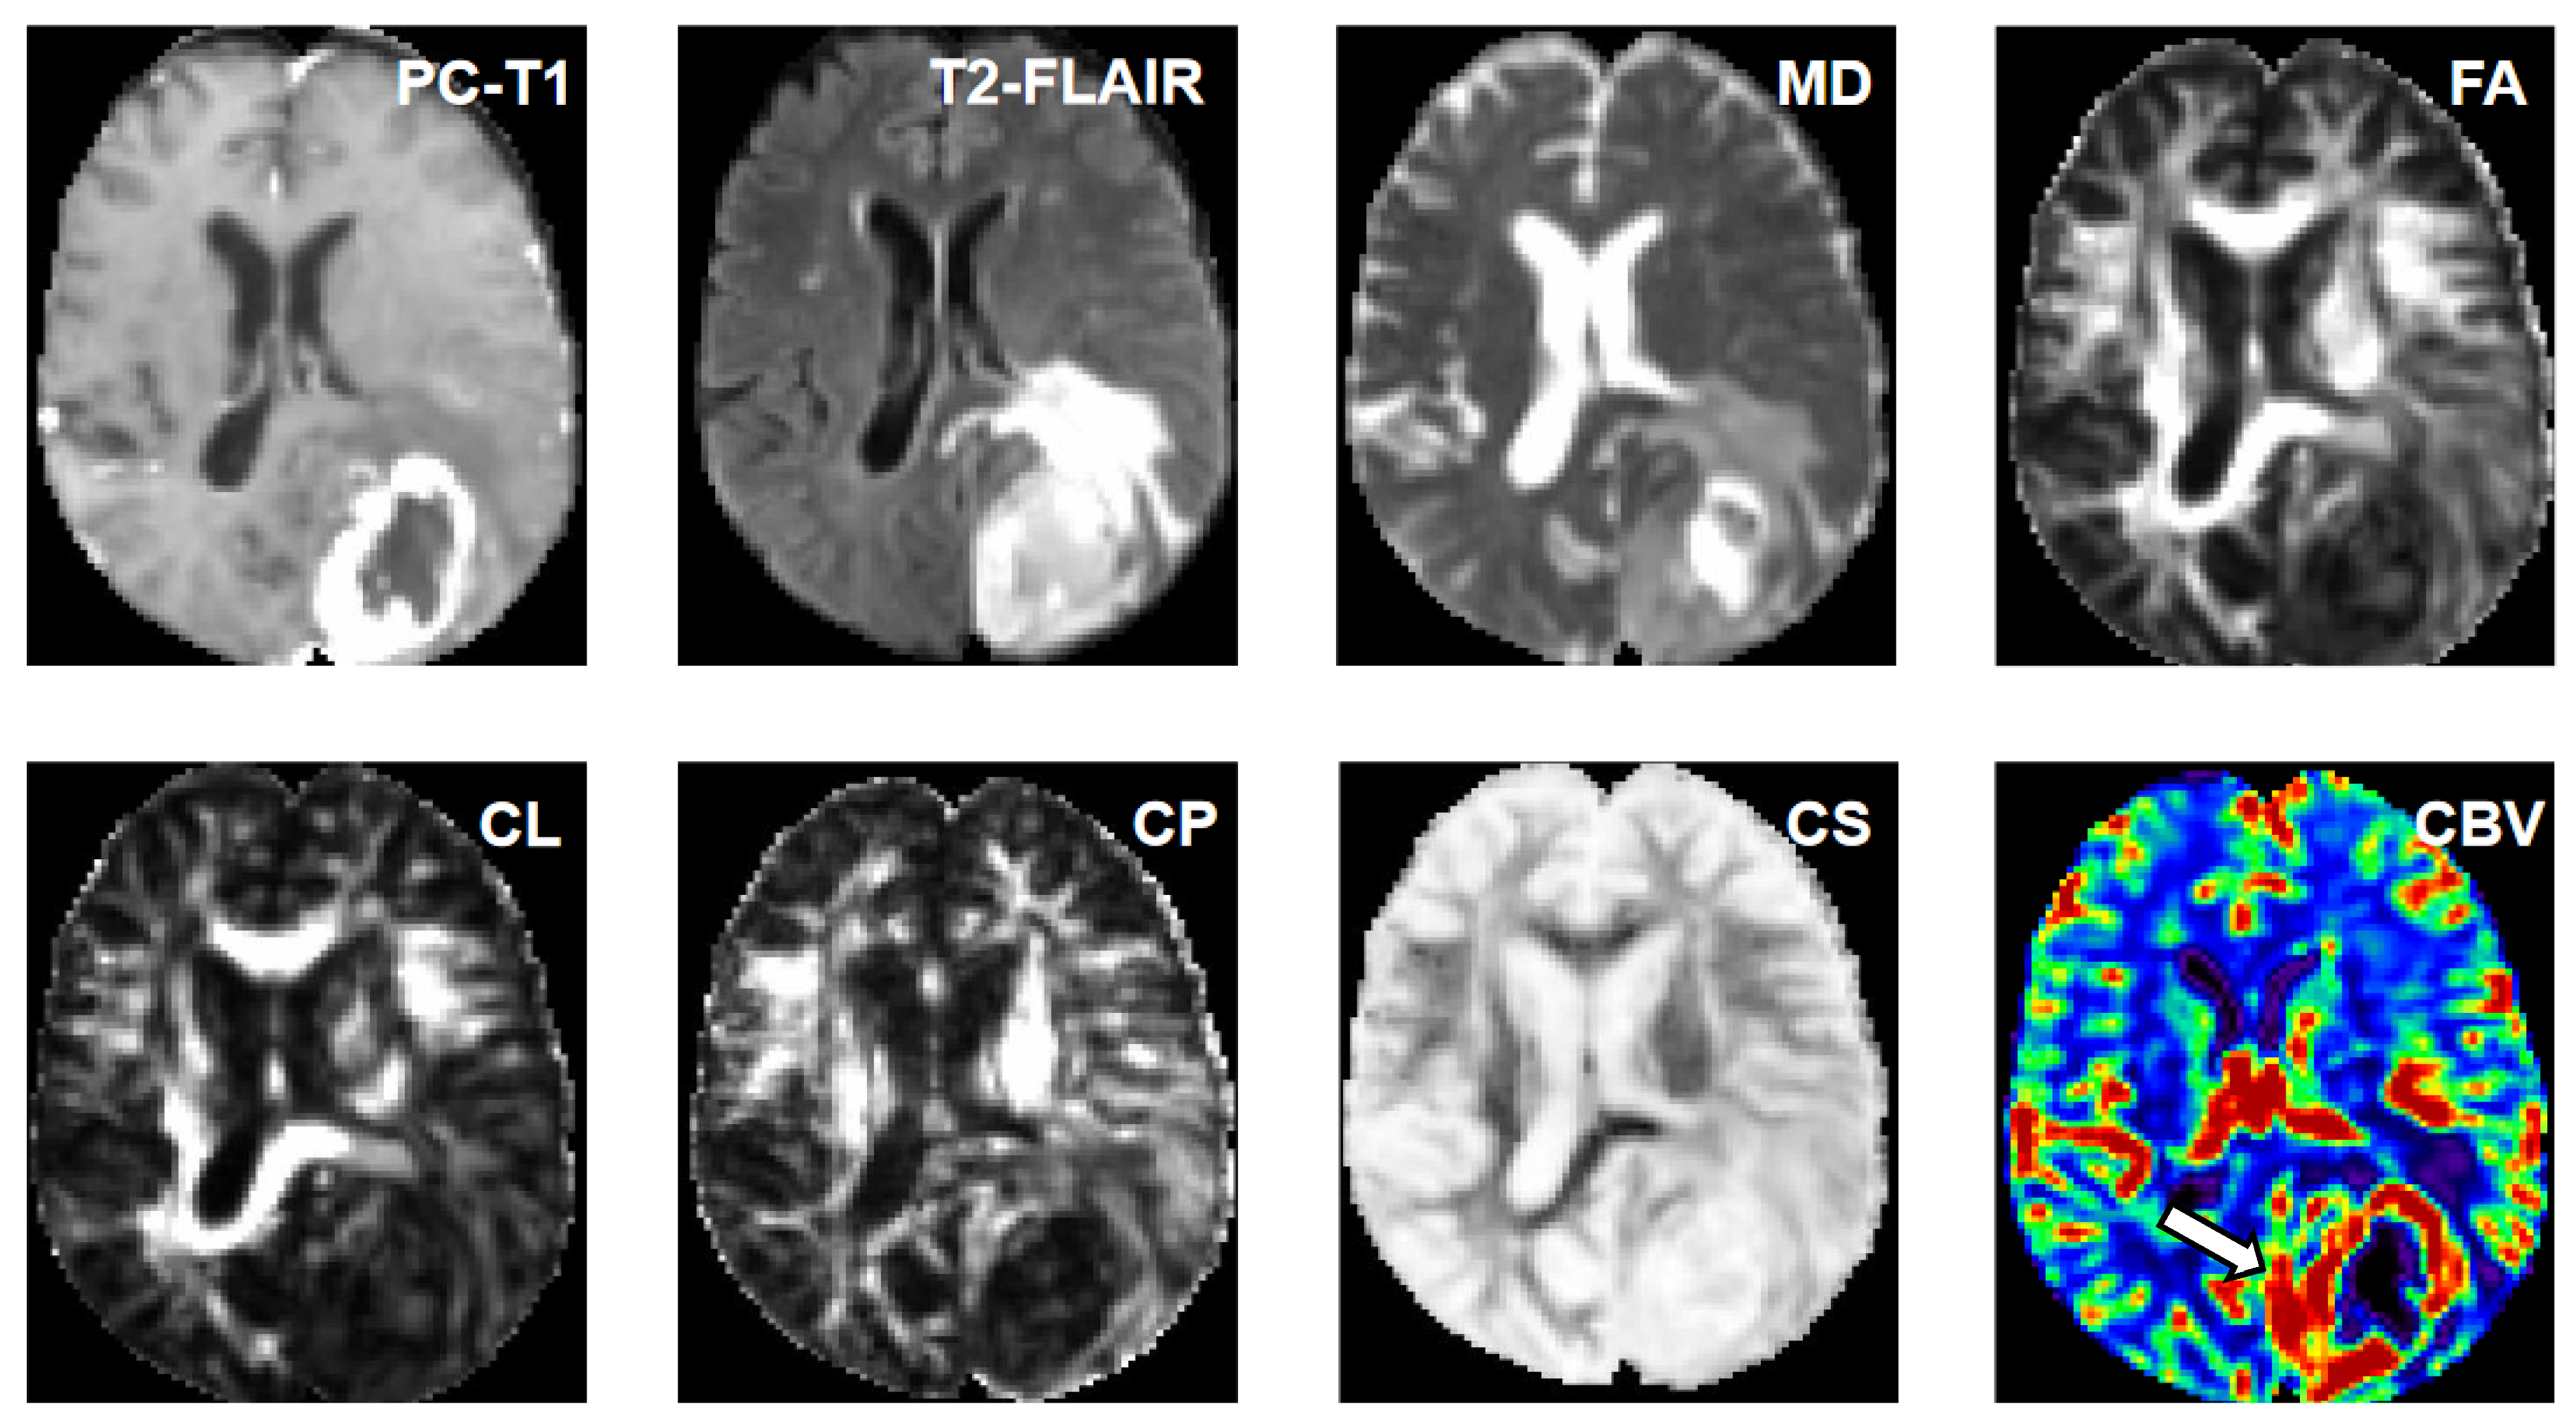

2.3. Diffusion Tensor Imaging

2.4. Dynamic Susceptibility Contrast–Perfusion-Weighted Imaging

2.5. Image Processing and Estimation of Quantitative Parameters